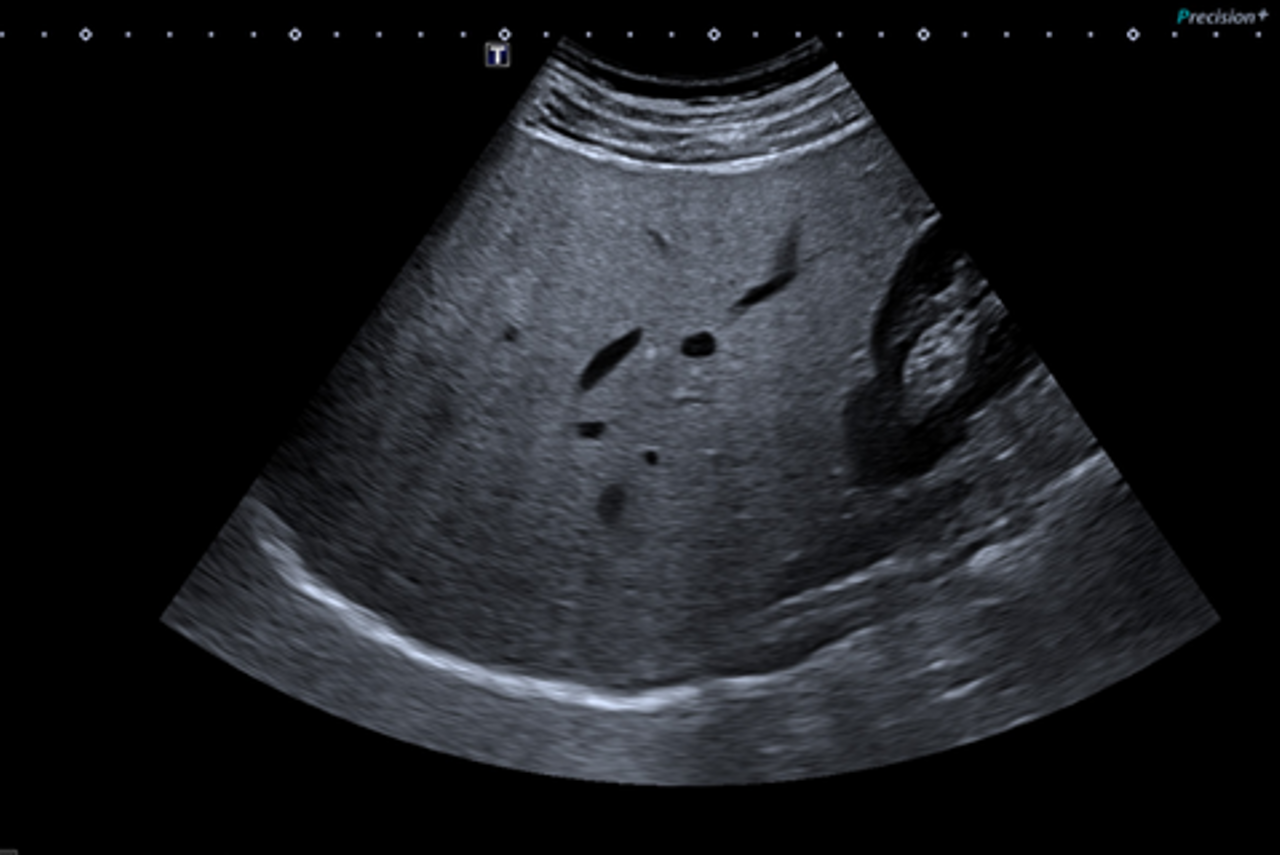

A Liver Health Assessment combines ultrasound imaging with two non-invasive technologies:

- Liver elastography measures liver stiffness

- Fat quantification measures the amount of fat in the liver

Together, these provide a valuable assessment of liver health.

Getting ready – You will lie down on a bed and your abdomen will be uncovered. A warmed gel will be applied to your skin to help the ultrasound probe move smoothly.

The scan – The sonographer will gently move the probe over the right side of your abdomen, between the ribs. You may be asked to change position or hold your breath for short periods.